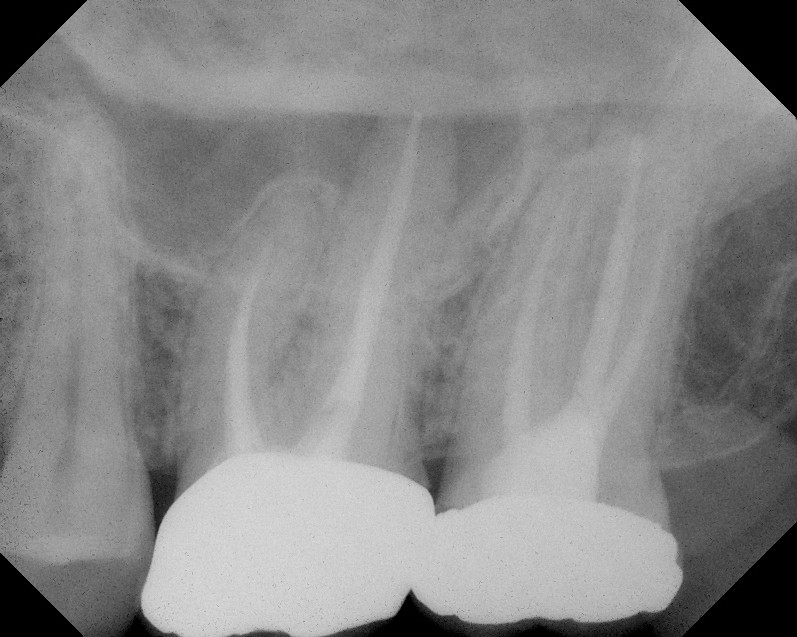

A TEC and CEC in mandibular molars. The occlusal view from microCT

A TEC and CEC in mandibular molars. The occlusal view from microCT Ct Endo Associates Removal of wisdom teeth, dental. Connecticut endodontic associates is a group practice with 2 locations. Connecticut endo manchester 360 tolland turnpike suite 2a manchester, ct 06042 phone: Currently connecticut endodontic associates's 2 physicians cover 2. Endocrine associates of connecticut in hamden and branford, ct, includes specialists dr. 2.4 miles away from connecticut endodontic associates we specialize in oral & maxilliofacial. Ct Endo Associates.